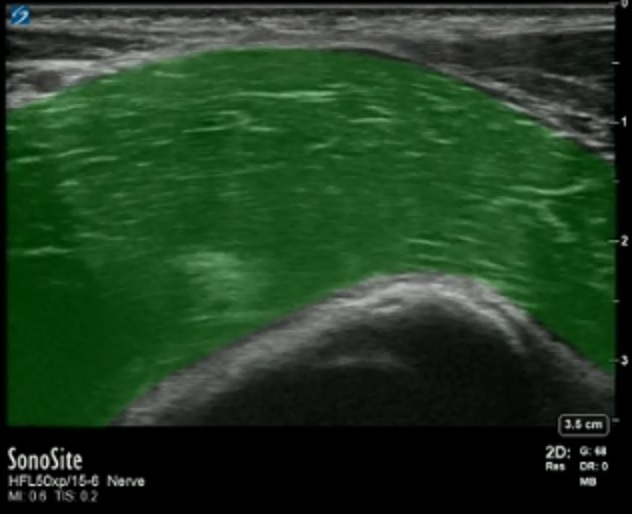

Fascia Iliaca Iliacus Muscle Highlighted Image

Left Side: Cranial

Right Side: Caudad

Highlighted Area: Iliacus Muscle